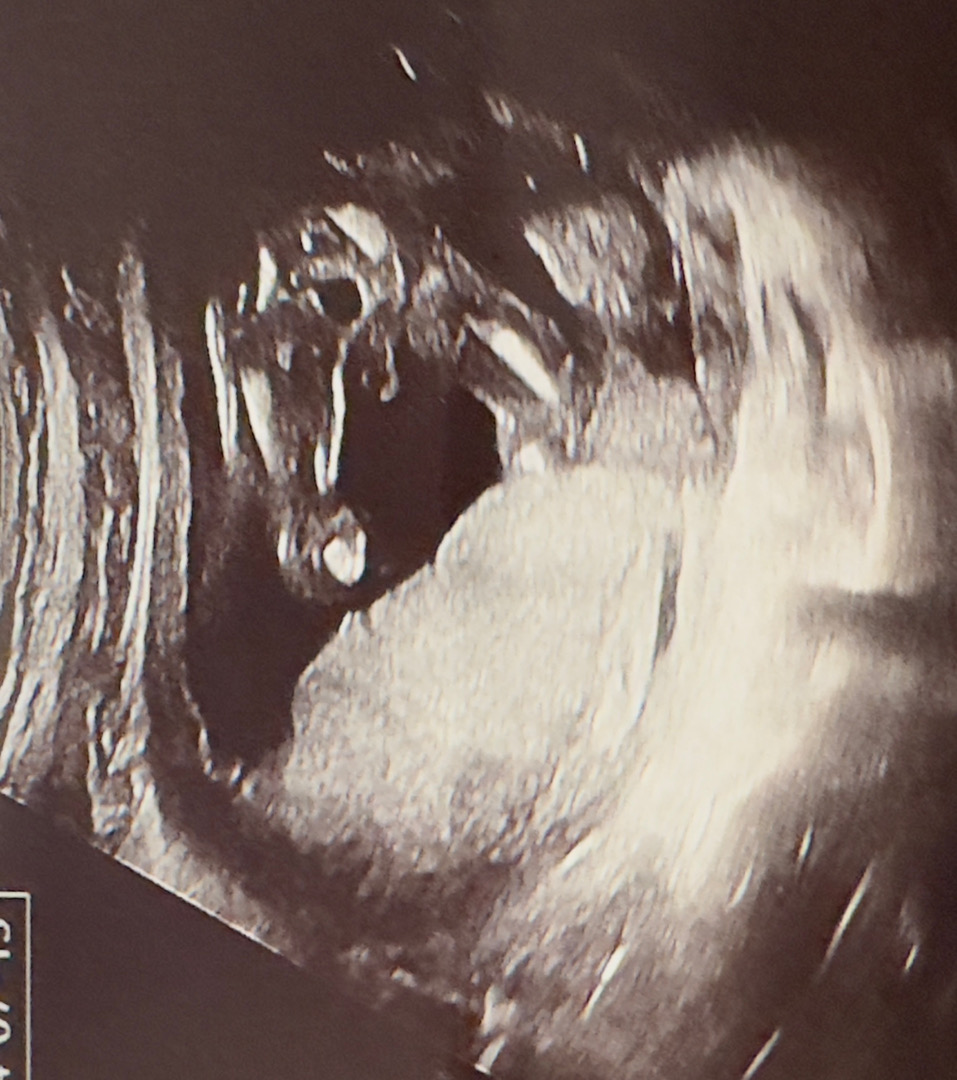

16주차 아들확정

너무 자기주장이 확실해서 ㅋㅋㅋ 남편은 딸이길 바랬는데 다시봐도 아들이죠?ㅋㅋ